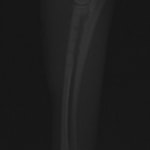

ペルシャ猫 11ヶ月齢 雄

他院にて左大腿骨遠位の成長板骨折(salter-harrisⅠ型)が認められており、治療相談を目的として来院。当院にて、キルシュナーワイヤーを用いたピンニングにより骨折部位の整復を行いました。術後の経過は良好で、現在も経過観察中です。

術前レントゲン